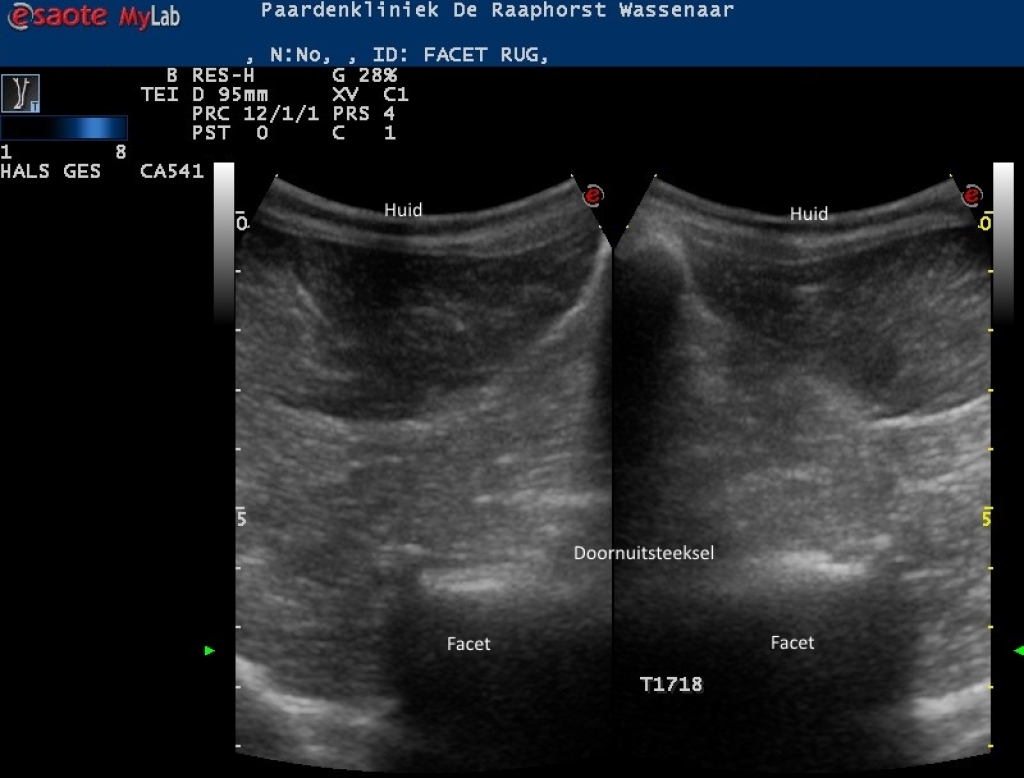

Links: Echografisch beeld van normale facetgewrichten van de borstwervels

Rechts: Echografische beeld van normale facetgewricht van de lendenwervels

Echografisch beeld van normale facetgewrichten van de borstwervels

Echografische beeld van normale facetgewricht van de lendenwervels